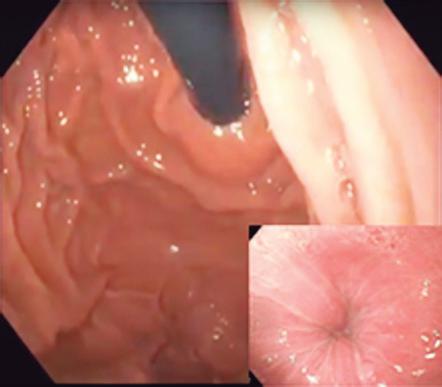

CASOS CLÍNICOS Biopsia guiada por ecoendoscopía como herramienta diagnóstica mínimamente invasiva para metástasis mesorrectal de carcinoma de células claras renales: reporte de caso

Nicole Marie Kahn, Mayra Florencia Defanti, Yanina Gabriela Carlino